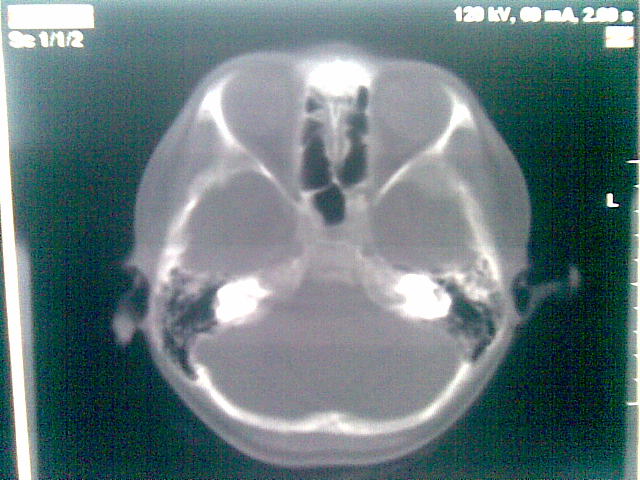

以下是引用随光逐影在2010-1-5 16:32:00的发言:[br]1)鞍上池囊性占位性病变,不排除蛛网膜囊肿可能;建议行mri检查。2)脑积水。

以下是引用yangyang2000在2010-1-5 20:41:00的发言:[br])鞍上池囊性占位性病变,不排除蛛网膜囊肿可能;建议行mri检查。2)脑积水

以下是引用yangyudong333在2010-1-5 21:28:00的发言:[br]1)鞍上池囊性占位性病变,不排除蛛网膜囊肿可能;建议行mri检查。2)脑积水。